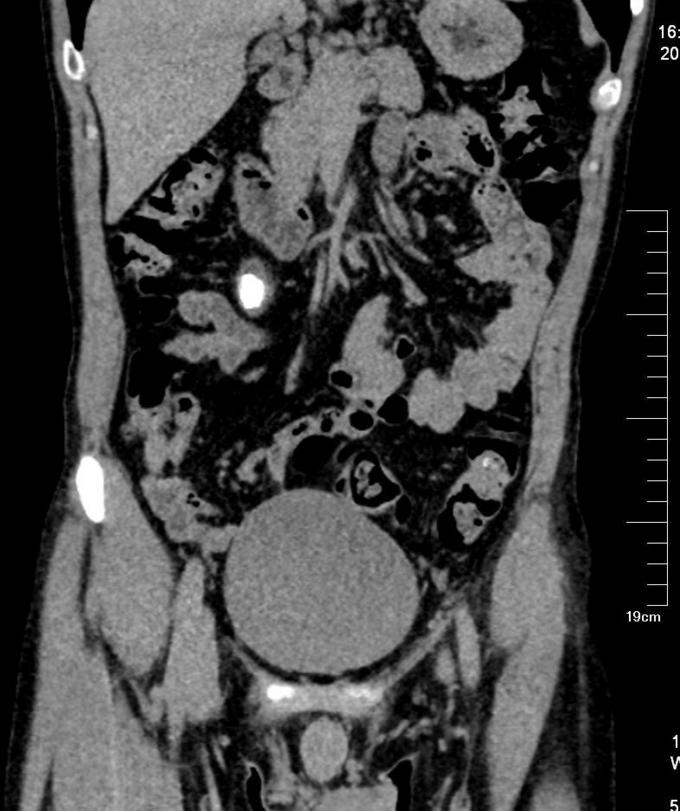

查体:右肾区明显压痛及叩击痛,左肾区无叩痛。右输尿管区轻微压痛,左输尿管区无压痛。膀胱区无明显隆起,未及包块,无压痛,叩诊无浊音。 辅查:我院泌尿系平扫CT+三维重建检查提示:右输尿管上段多发结石,右肾及输尿管重度积水,右肾萎缩。左肾盂略宽,结合临床。 我院肾图检查提示:1.右肾符合积水改变,功能重度受损。2.左肾GFR正常范围,功能正常。

诊断:右输尿管结石合并右肾重度积水。 治疗:给予右侧输尿管切开取石术。